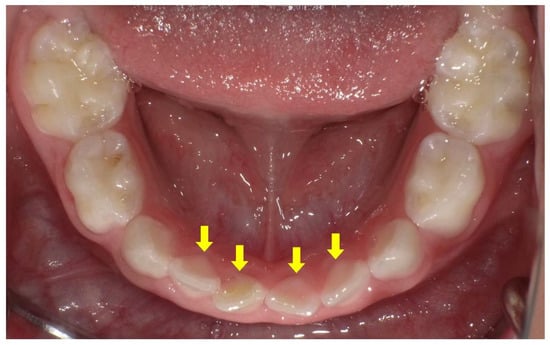

- Wato, K.; Okawa, R.; Matayoshi, S.; Ogaya, Y.; Nomura, R.; Nakano, K. X-linked hypophosphatemia diagnosed after identification of dental symptoms. Ped. Dent. J. 2020, 30, 115–119. [Google Scholar] [CrossRef]

- Okawa, R.; Hamada, M.; Takagi, M.; Matayoshi, S.; Nakano, K. A Case of X-Linked Hypophosphatemic Rickets with Dentin Dysplasia in Mandibular Third Molars. Children 2022, 9, 1304. [Google Scholar] [CrossRef]